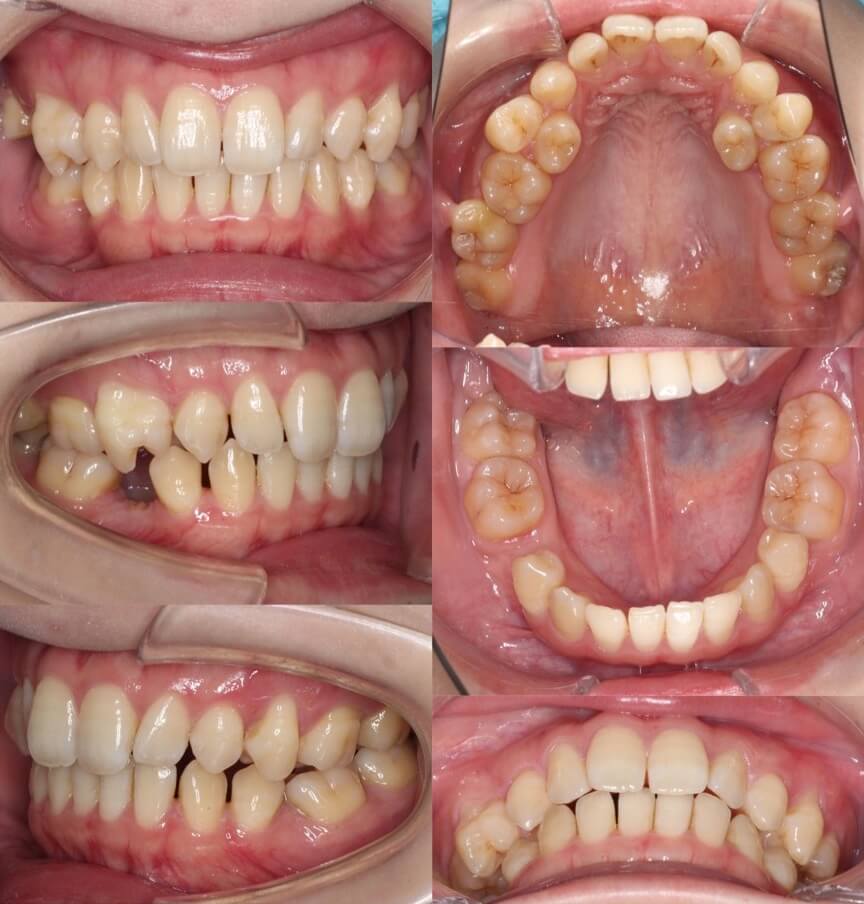

40代女性・先天性欠損2歯・下5欠損

横顔の突出だけではなく、歯茎が少し見えることも気にされていました。下顎ができるくらいまでしっかりと前歯を後方移動させたいという希望からアンカースクリューを使用し前歯を後退させました。先天性欠如の下5番のスペースは乳臼歯があったこともあり、抜歯後は大きく空隙が開きましたが、しっかりと空隙閉鎖を行いました。

<症例概要>

主訴:横顔の突出・ガミースマイル

年齢・性別:40代女性

症状:左右下5番欠損・開咬・下顎後退

治療方針:抜歯空隙閉鎖・下顎臼歯近心移動・

抜歯:上左右4番・下左右乳臼(計2本)

固定装置:歯科矯正用アンカースクリュー

治療装置:唇側矯正装置

治療期間:2年4か月

リテーナー:上下プレートタイプ

治療費用:990,000(税込)

代表的副作用:痛み・治療後の後戻り・歯根吸収・歯髄壊死・歯肉退縮